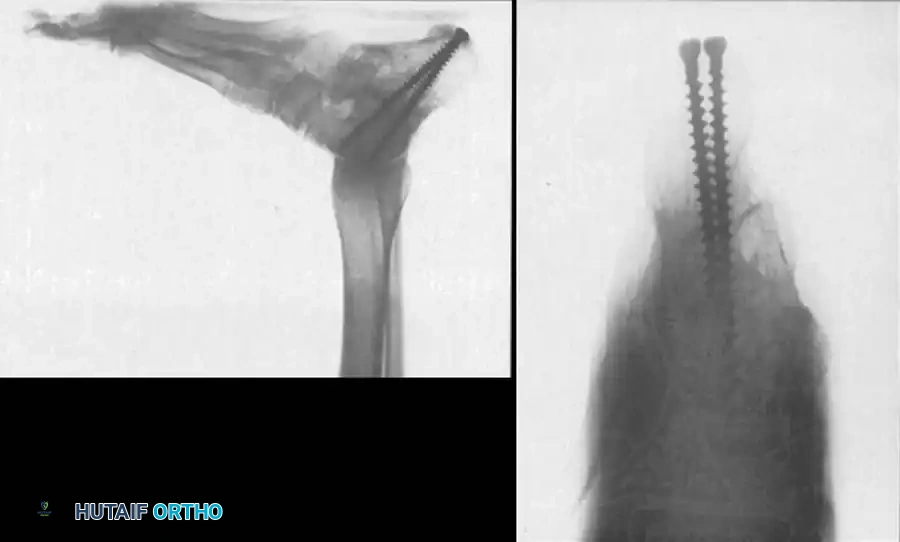

Fixation and Radiographic Confirmation

Rigid fixation is typically achieved with large-diameter (6.5mm or 7.3mm) cannulated cancellous screws placed from the posterior calcaneal tuberosity into the talar body and neck.

Lateral radiograph demonstrating robust screw fixation across the subtalar joint following realignment.

Coronal CT scan confirming solid osseous integration of the bone block and hardware placement within the subtalar joint.

Final lateral radiograph showing restored talocalcaneal alignment and a solid fusion mass.